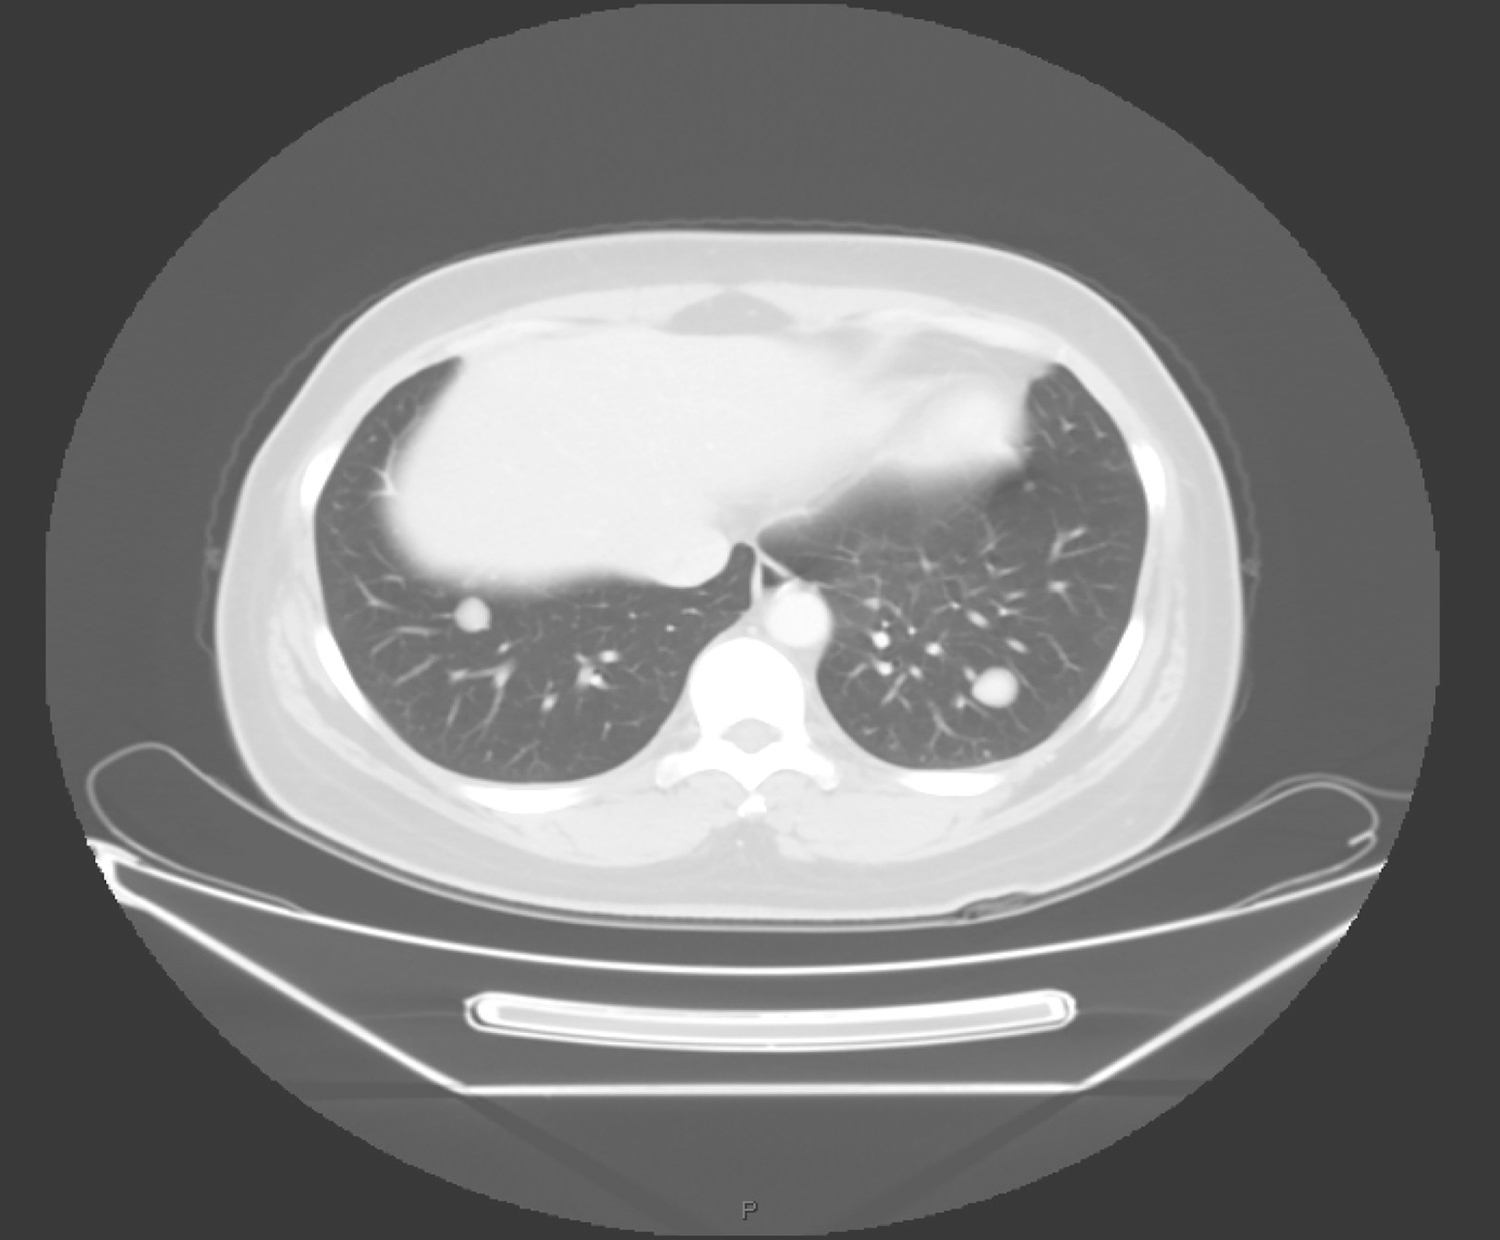

甲状腺弥漫不规则增大,密度不均匀,右叶为著,内有多发高、低密度结节影,大者最大截面约2.5cm×2.2cm,边界不清,增强扫描呈不均匀强化,向下伸入上纵隔胸骨后(图1);另见甲状腺左叶低密度结节,大小约1.6cm×1.0cm,不均匀轻中度强化。右侧颈部、锁骨水平及上纵隔区可见多发结节及肿物影,呈多结节融合状,最大截面约5.1cm×3.6cm,部分层面似与甲状腺右叶肿物相连续,包绕右侧颈动脉鞘,压迫右侧舌骨及下咽腔,增强扫描呈明显强化(图2)。双肺可见多发结节影,大者约1.9cm×1.4cm,边界清楚,明显强化(图3)。

图3 胸部增强CT示双肺可见多发结节影明显强化